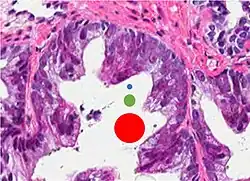

Acinar adenocarcinoma with multiple nucleoli. -

Acinar adenocarcinoma with double and eccentric nucleoli.